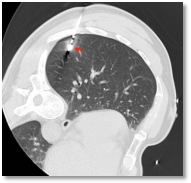

CT引导下肺结节消融术

CT引导下肺结节消融术 | CT引导下肺结节消融术 | 手术伤口 |